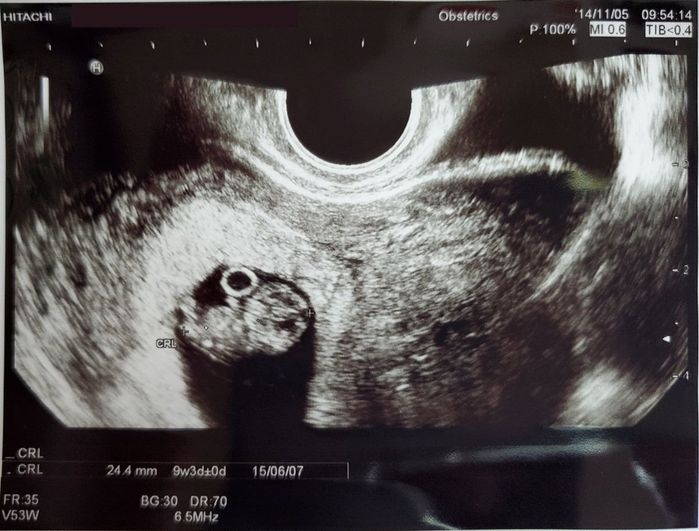

妊娠9週目のエコー写真 - あ!赤ちゃんの姿になってる!

赤ちゃんの無事を祈りながら見つめたモニターには、赤ちゃんのシルエットがありました。まだとても小さいのに立派な頭と胴体とかわいい手足ができています。「つわり」はあるものの、おなかに赤ちゃんがいる実感がなかった私。この時にやっと「本当に妊娠したんだな」と感じたのでした。赤ちゃん横の丸いリングは「卵黄のう」だと教えていただきました。